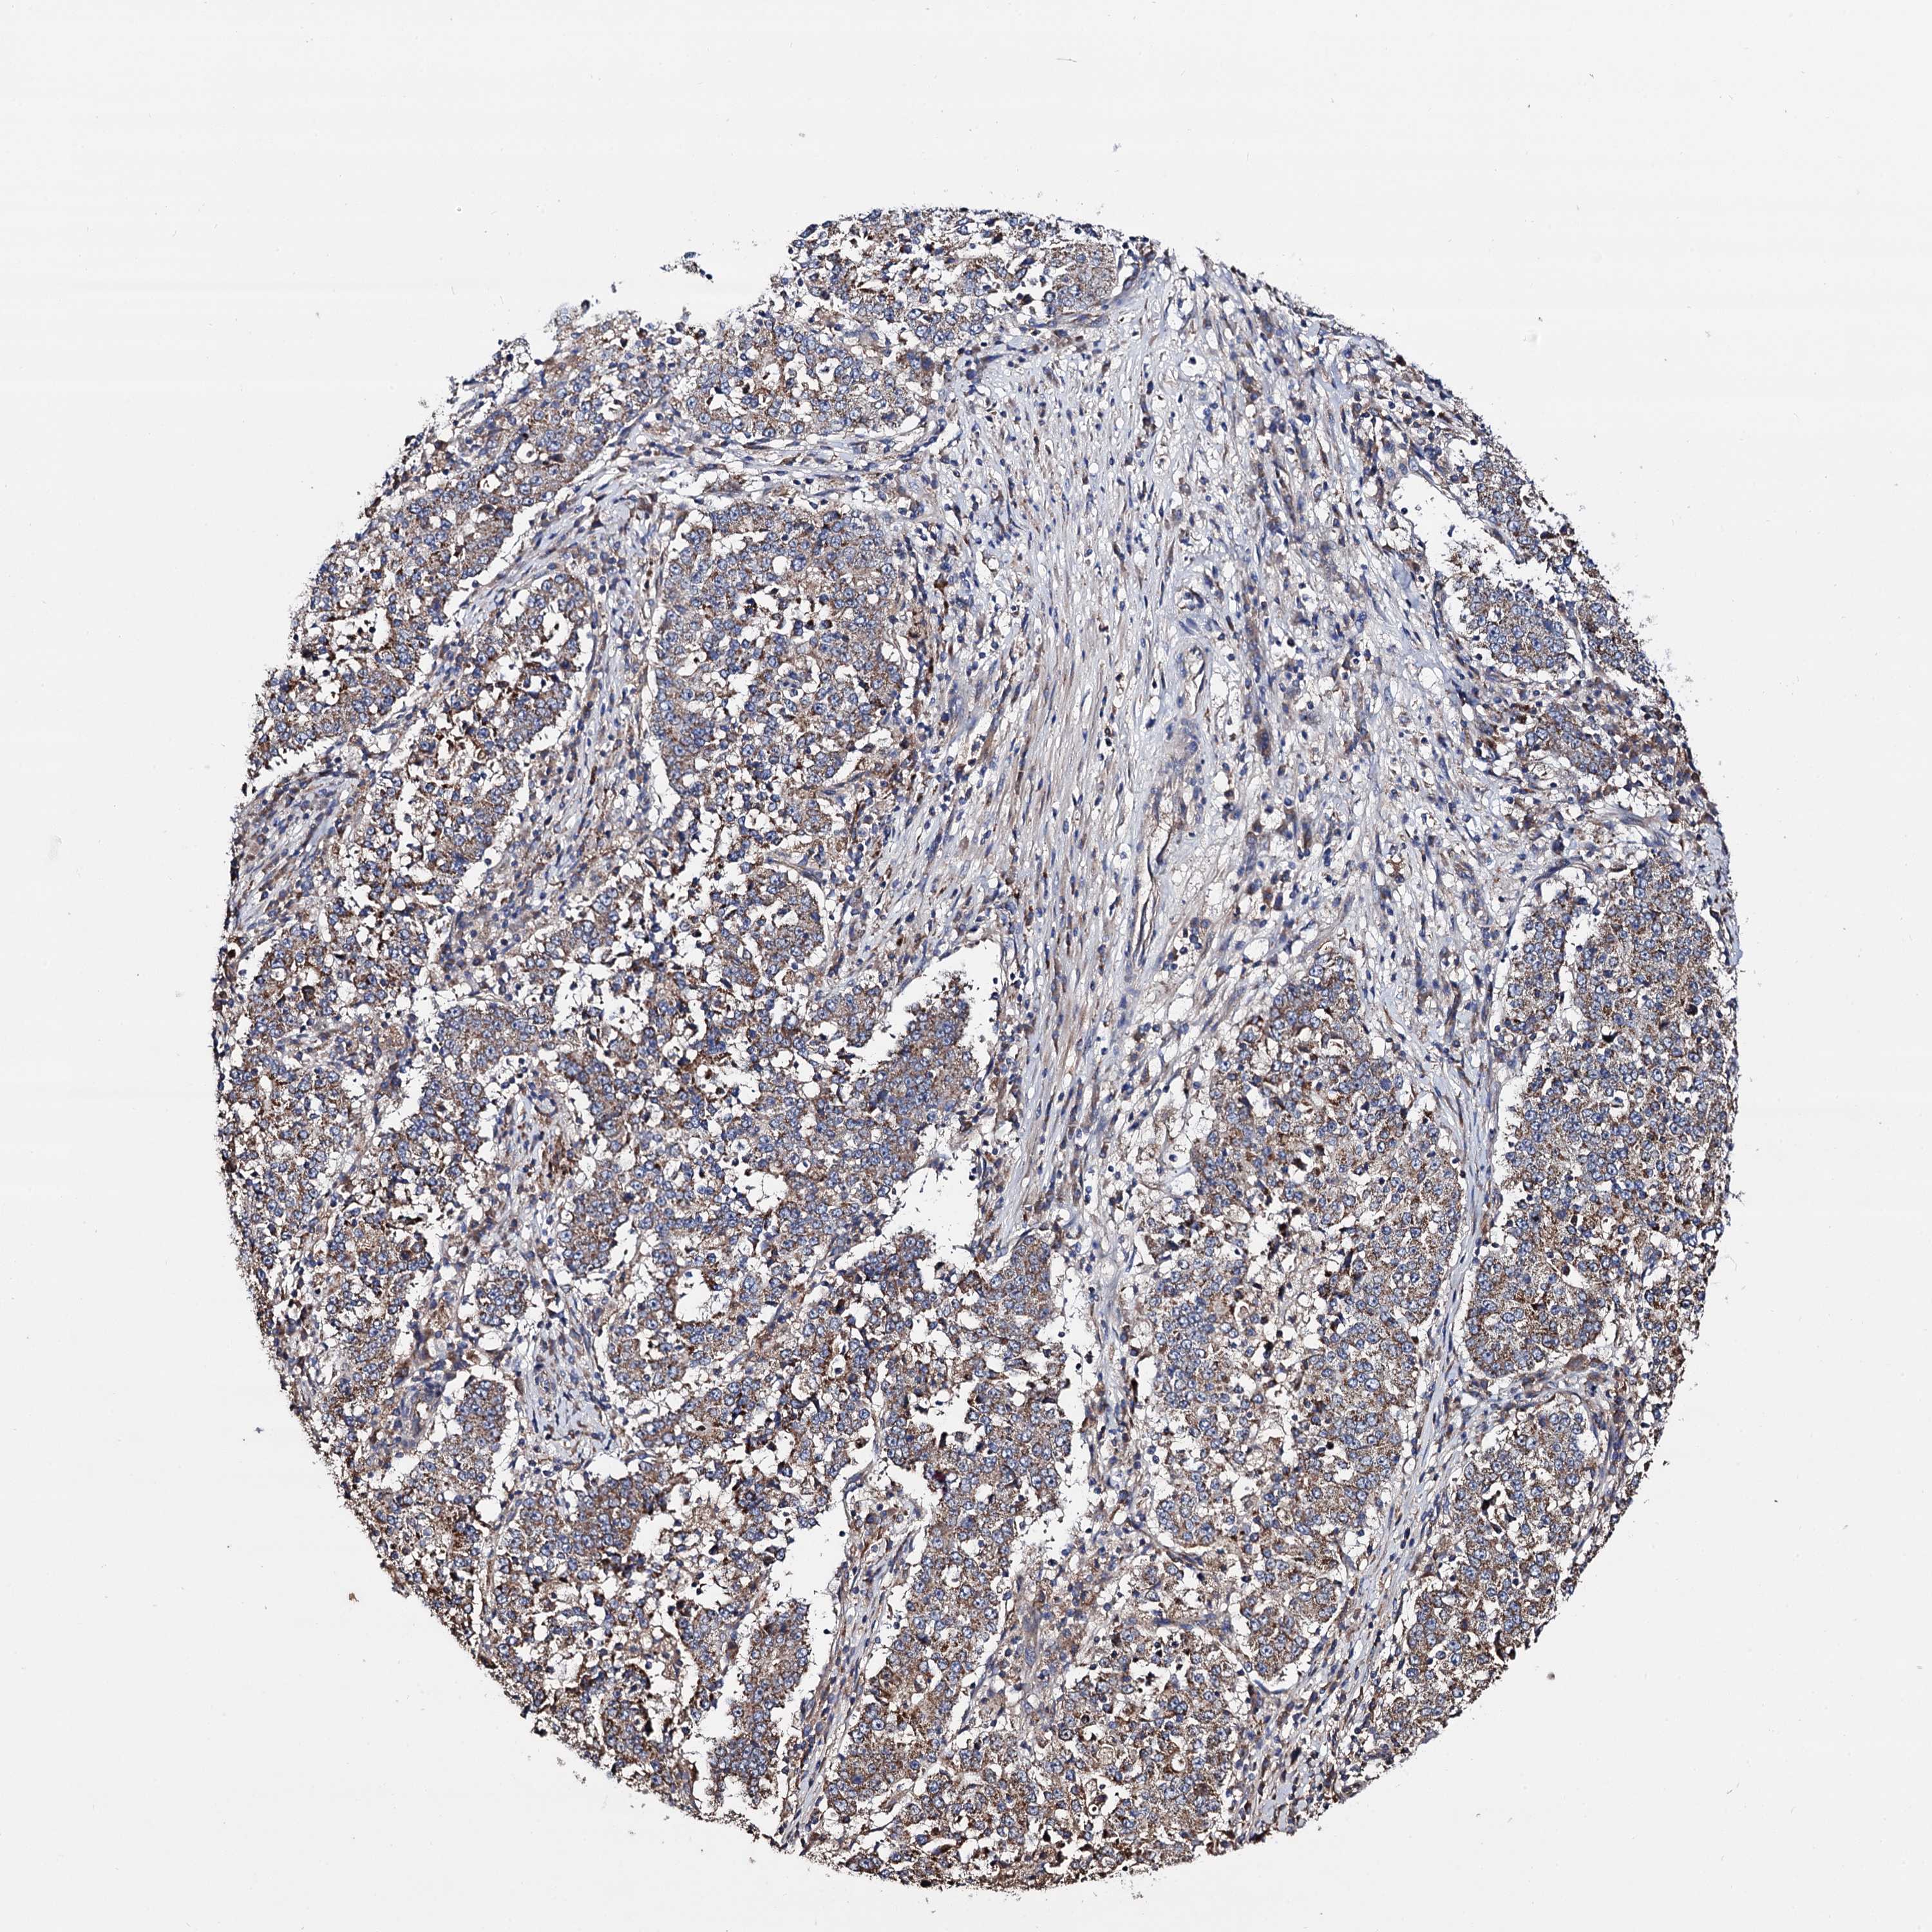

STOMACH CANCER - Protein expressioni

A mouse-over function shows sample information and annotation data. Click on an image to view it in a full screen mode. Samples can be filtered based on level of antibody staining by selecting one or several of the following categories: high, medium, low and not detected. The assay and annotation is described here.

Note that samples used for immunohistochemistry by the Human Protein Atlas do not correspond to samples in the TCGA dataset.

Antibody stainingi

Antibody staining in the annotated cell types in the current human tissue is reported as not detected, low, medium, or high, based on conventional immunohistochemistry profiling in selected tissues. This score is based on the combination of the staining intensity and fraction of stained cells.

Each image is clickable and will lead to virtual microscopy that enables deeper exploration of all samples and also displays staining intensity scores, fraction scores and subcellular localization as well as patient and tissue information for each sample.

Antibody HPA040845

Staining

High

Medium

Low

Not detected

Intensity

Strong

Moderate

Weak

Negative

Quantity

>75%

75%-25%

<25%

None

Location

Nuclear

Cytoplasmic/membranous

Cytoplasmic/membranous,nuclear

Adenocarcinoma, NOS

Adenocarcinoma, High grade